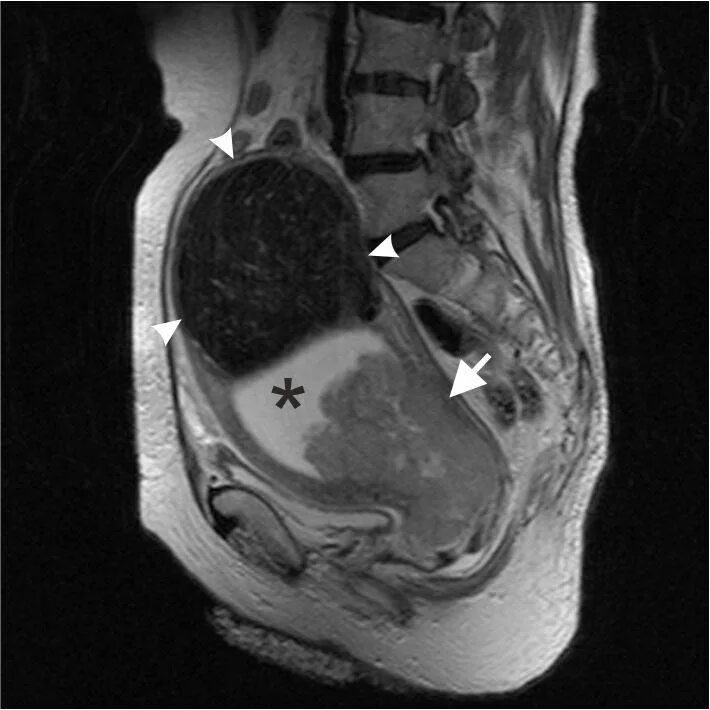

Можно ли сделать мрт малого таза